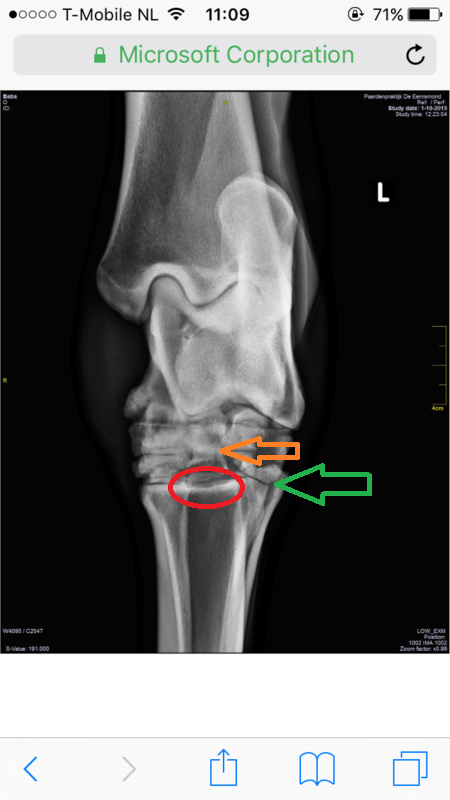

Babs was nooit makkelijk met haar achterbenen en soms ietwat stijf, maar toen ik haar heb laten keuren, bleek dit geen probleem. Ook de buigproef is ze doorgekomen en verder nooit kreupel geweest. Maar sinds eind augustus liep Babs kreupel, eerst hebben we het even aangekeken, maar het werd niet beter, daarom hebben we besloten haar op de foto te zetten, daar kwam uit dat ze spat heeft en een wat ernstigere vorm. Ook vertelde de dierenarts dat ze al spat had, maar dat, dat vergroeid is, waar ze nu last van heeft is "nieuwe" spat met botoplossingen. Babs loopt op het moment behoorlijk kreupel, maar is verder zichzelf, lekker actief en alert.

Foto's:

Voor degene die benieuwd zijn naar de foto's